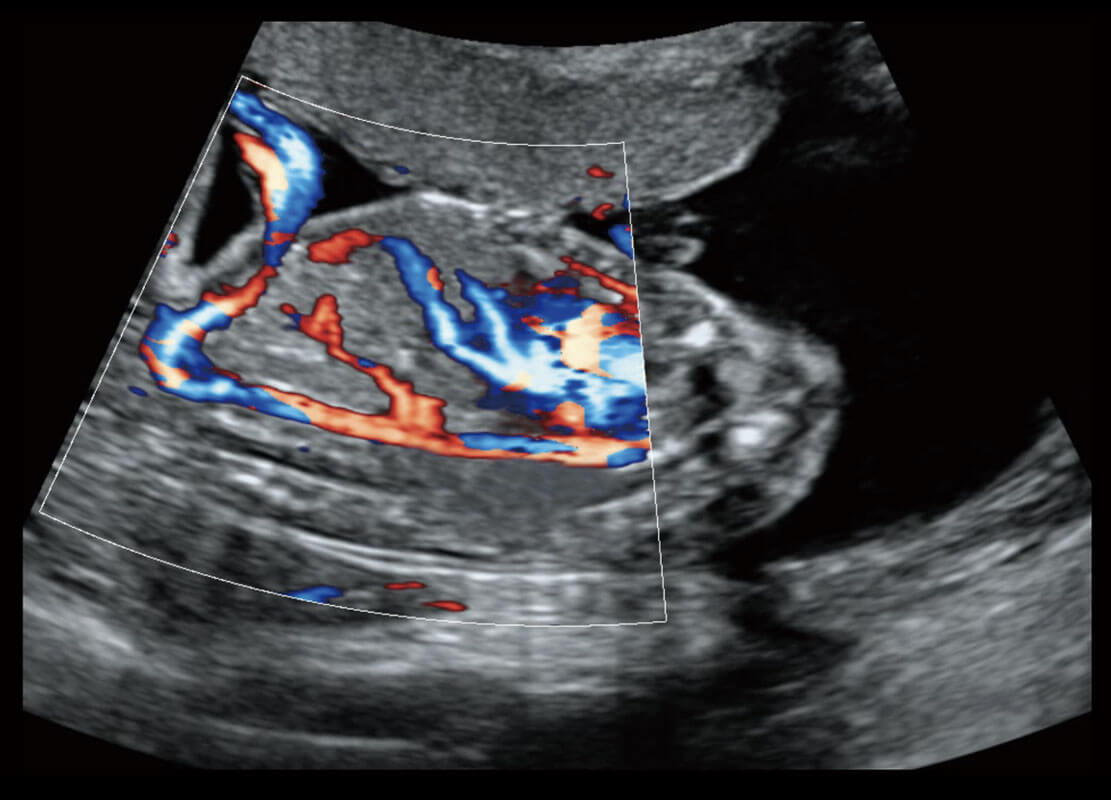

生殖健康

P60优异的图像质量搭载专科探头,在妇科基础疾病的诊断、卵泡生长的监测、输卵管通畅情况的判别等方面为您提供生殖应用方案。

• 腔内妇科-宫腔分离

• 腔内妇科-卵巢

• 腔内三维-宫内节育器

• 腔内三维-光影成像